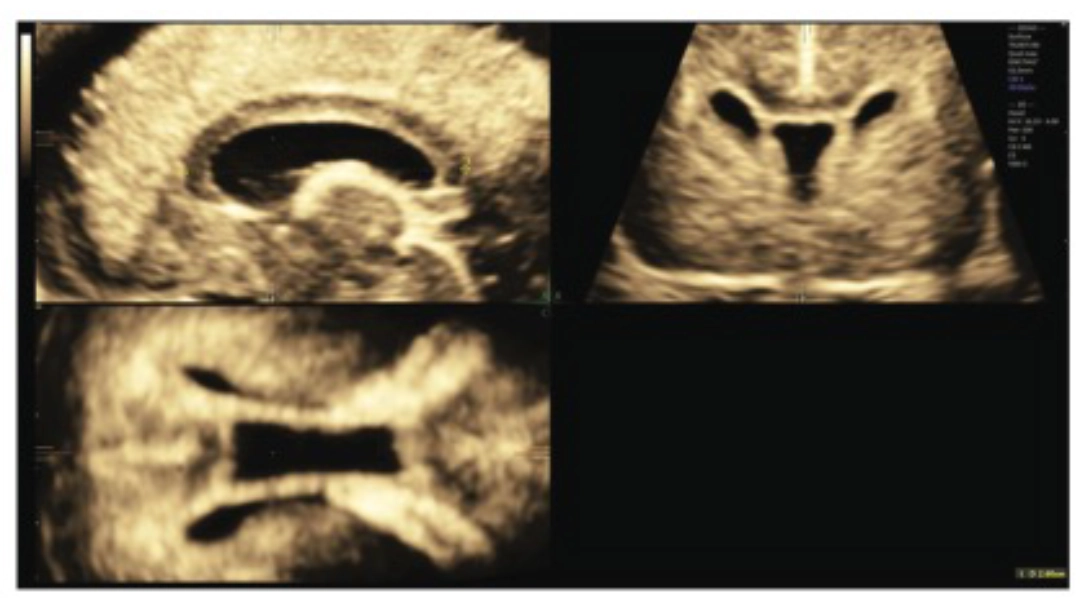

Ejemplo de plano sagital obtenido por ecografía transvaginal 3D, mostrando la medición de la longitud del cuerpo calloso en un feto de 22+3 semanas. Esta alineación precisa fue clave para la calidad y confiabilidad de los datos del estudio.

Las mediciones se realizaron en volúmenes obtenidos solo por vía transvaginal, con alineación exacta del plano sagital a través de imágenes multiplanares. Esto elimina errores de interpretación frecuentes en estudios que usan imágenes transabdominales.